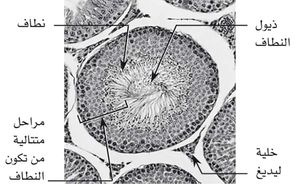

تُنتَج الحيوانات المنوية عن طريق انقسامين إنتصافيين Meiotic للخلايا الإنتاشية Germ cells والتي تُبطن نُبيبات ناقل المني Seminiferous tubules الملتوية الموجودة في الخصية. بلغ طول خصية الثور (الشكل 1) نحو 10ـ12سم، وعرضها 5ـ7سم، وتزن نحو 300 ـ 400 غرام، وهي عمودية الاتجاه. يصل طول نُبيبات ناقل المني إلى 5 كيلومترات في الثور وهي تُمثل الجزء الأكبر للخصيتين. موجودة ضمن فصوص «حجرات» مكونة من امتدادات من الغِلالة البيضاء، ومحتوية على خلايا تناسلية في مراحل مختلفة من العمر والتمايز الخلوي (ظِهارة إنتاشية germinal epithelium، منسليات منوية spermatogonia، خلايا نطفية (منوية) spermatocytes ابتدائية وثانوية، ومنويات (أرومات النطاف) spermatids، ونطاف spermatozoa، وخلايا سرتولي Sertoli cells. ويوضح الجدول (1) مقارنة للخصى عند بعض أنواع الحيوانات. تُنتج خصيتا الثور البالغ حوالي 1,2 إلى 1,8 بليون حيوان منوي في الملي لتر الواحد، وبمعدل 4-8 ملِ من المني في القذفة الواحدة. إن كمية الحيوانات المنوية المُنتجة لها علاقة مباشرة بوزن الخصيتين ووزن الثور، كلما كان الثور أضخم أو أكبر، كلما أنتج كمية أكبر من الحيوانات المنوية، أكثر من الثيران الشابة أو الصغيرة الحجم.[1]

يمتلك النسيج البيني interstitial tissue الموجود بين الأنابيب المنوية خلايا تدعى خلايا ليدك Leydig cells، وهي المصدر الرئيس للأندروجينات androgens (ومن أهمها التستوسترون testosterone) (الشكل 2). ويتم تنظيم إفراز هذه الهرمونات بعلاقات دقيقة بين الخصية والهرمونين الموجهين للقُند (المنشطين لهرمونات الجنس) gonadotrophins من النخامى الأمامية، وهما الهرمون المنشط للجريب (الحاثة الجريبية) follicle stimulating hormone (FSH) والهرمون اللوتيئيني (الحاثة اللوتيئينية أو الملوتنة) luteinizing hormone (LH). كما تفرز الخصية كميات زهيدة من الإستروجين.